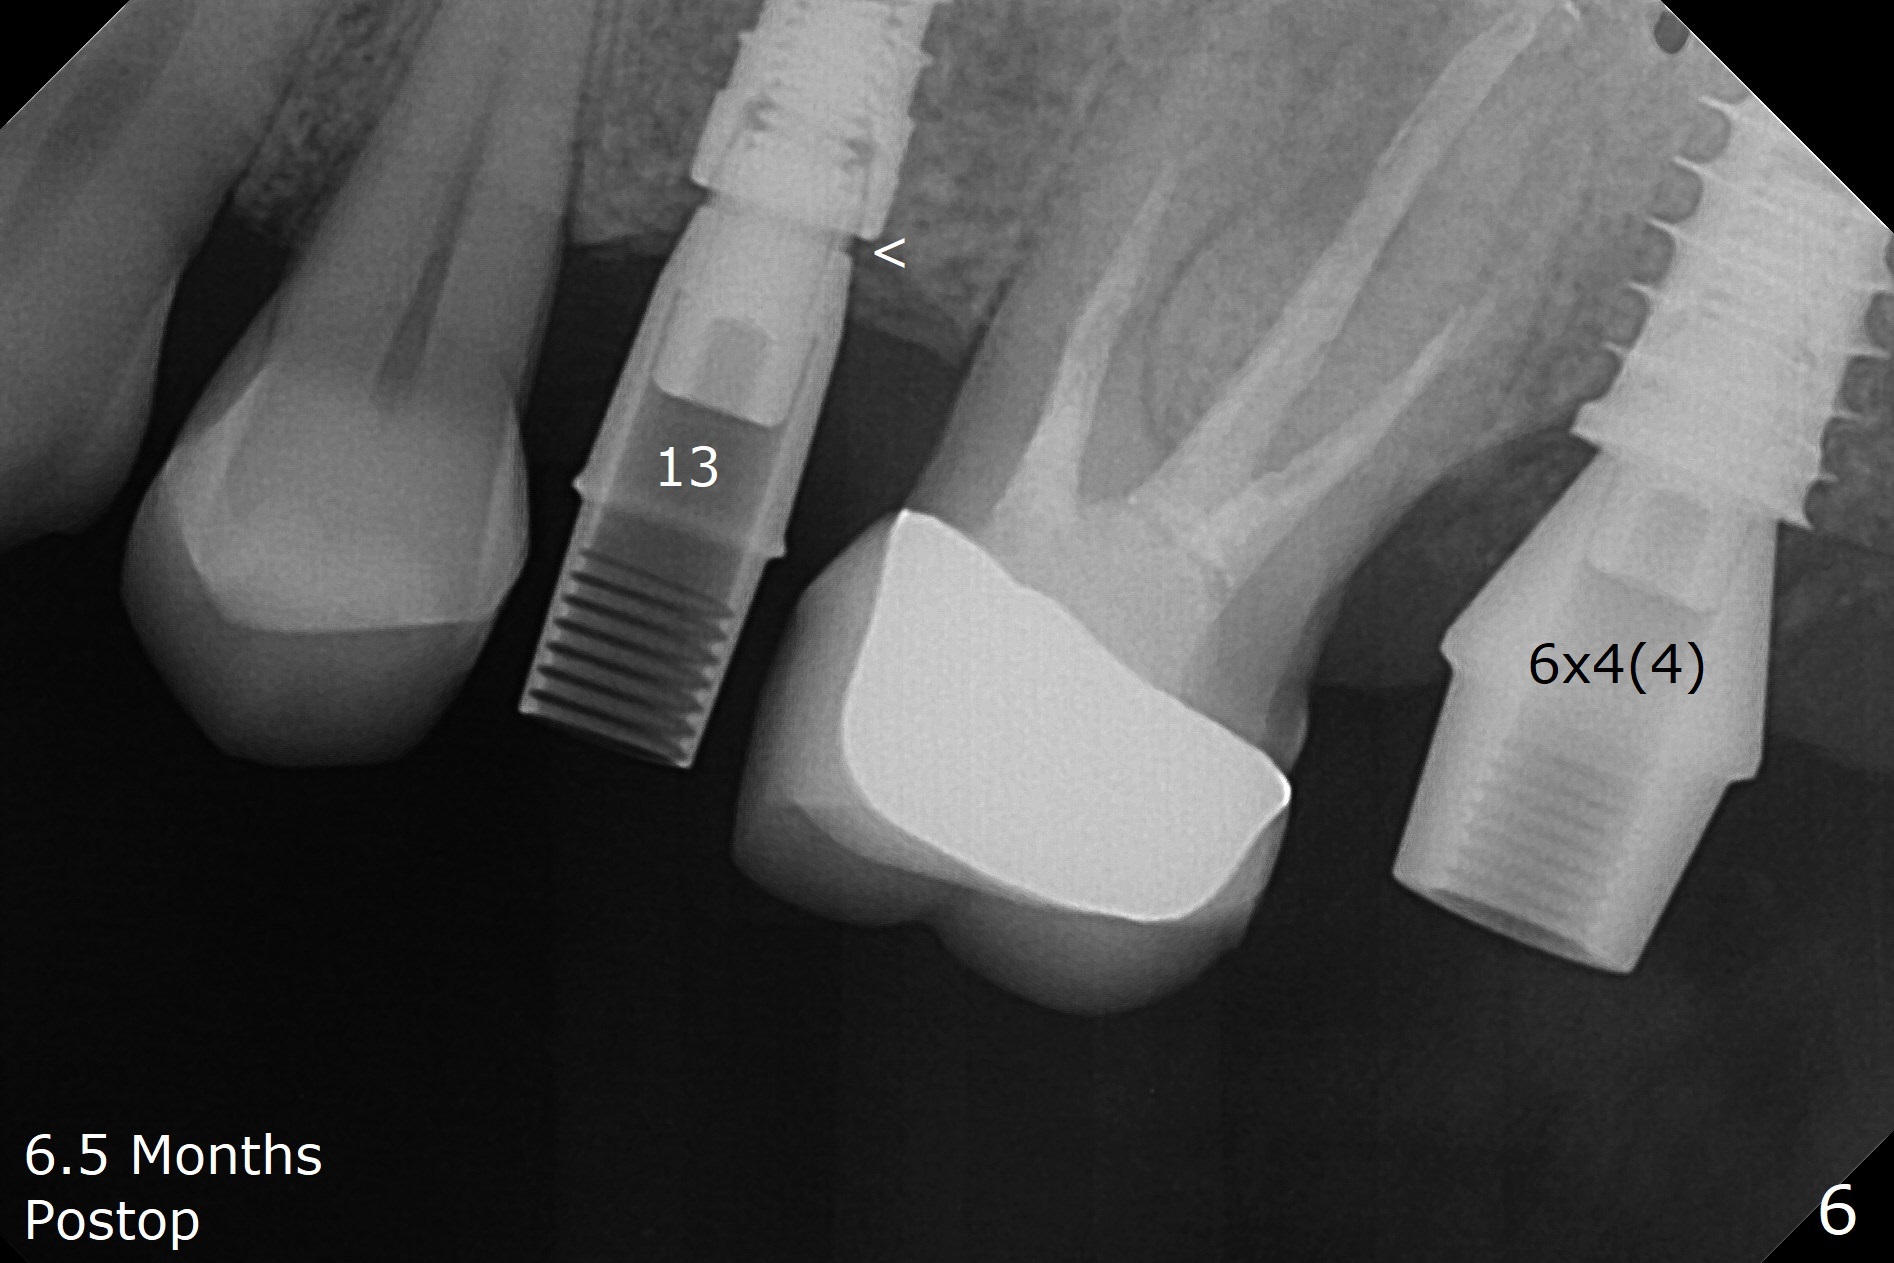

The palatal gingival margin of the tooth #15 with vertical root fracture is low, consistent with the low palatal plate after extraction (Fig.1 >). With IS guide, a 5x11 mm IBS implant is placed in the septum with >5 mm the palatal gap. After underprep in depth, a 3.5x9 mm achieves primary stability (Fig.2,3). The palatal defect is repaired with allograft (*) and 2 pieces of PRF membrane. The palatal soft tissue defect appears to have been repaired 6 months postop (Fig.4,5). When a narrower abutment with longer cuff is placed at #15 (6x4(4) mm in Fig.6, as compared to 6.5x4(3) mm one in Fig.2), there is no gap between the implant and abutment. In contrast there is one at #13 (Fig.6 <) when a 4x4(4) mm abutment is seated following removal of a 4x4 mm healing abutment. After use of a 4.6 mm profile drill, the gap disappears (Fig.7). Impression is taken.